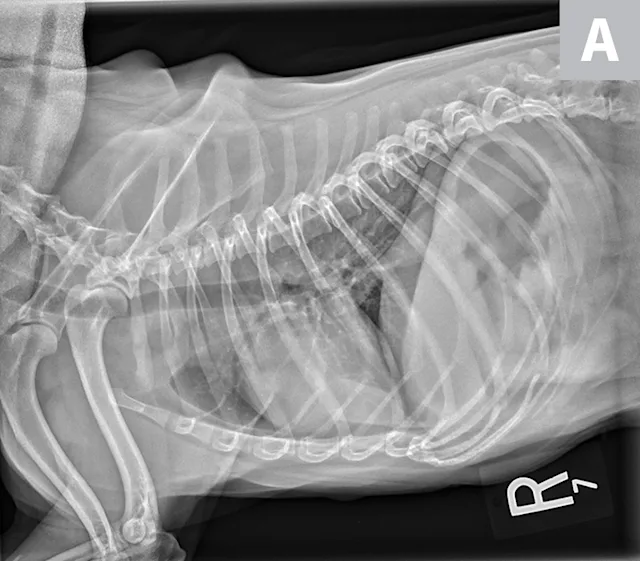

2. Cardiac Silhouette of Dogs on Thoracic Radiographs

The cardiac silhouette can appear larger in small-breed dogs because the heart occupies a large amount of thoracic space; conversely, the cardiac silhouette can appear smaller in large-breed dogs (eg, greyhounds) due to the relatively larger size of the thorax (Figure 3).2

FIGURE 3A

Relative heart size difference on lateral thoracic radiographs of a normal basset hound (A) and a normal greyhound (B).